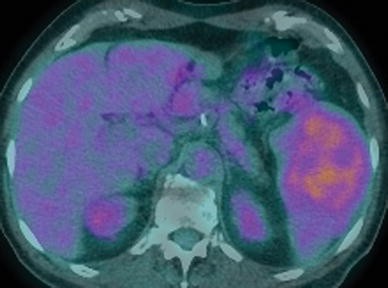

Fig. 1

figure 1

SANT of the spleen: 2-[18F]-Fluoro-2-Deoxy-D-Glucose (FDG-PET) findings. Axial fused image shows intense tracer activity (standard uptake value = 4.5) within the splenic lesion.

Only one prior published report of the FDG-PET behavior of splenic SANT is known [13]. These authors [13] indicated that splenic SANT shows hypermetabolic activity on FDG-PET, simulating neoplasm; our lesion showed similar behavior. The abundance of cells, including hemosiderin-laden macrophages, myofibroblasts, lymphocytes, and plasma cells, may account for splenic SANT’s FDG avidity.